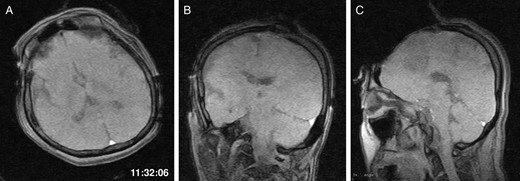

General anaesthesia was induced. Following left frontal craniotomy and dural incision, the first iMRI was performed (Fig. 1 ). One hundred fifty-eight minutes from induction, the patient regained consciousness after all anaesthetics were ceased. Tumour resection was performed with free conversation. However, after 143 min of surgery under the awake condition, the patient came to complain of excessive sleepiness though she could respond to verbal commands. Electrocorticogram (ECoG) did not detect after-discharge. The tumour was successfully removed en bloc fashion. Progressive brain swelling was not observed. The second iMRI was commenced 182 min into the awake phase (Fig. 2). Thirteen minutes from the beginning of the second iMRI scanning, the patient did not respond to noxious stimuli. When the patient was removed from the gantry, she was unconscious and had stopped spontaneous breathing. Her pupils were isocoria and did not dilate. Neither epileptic seizure nor anaphylactic reaction occurred. The peripheral oxygen saturation was not measurable, but cardiac instability or signs of vomiting were not observed. We decided to discontinue the operation under the awake status. No electrolyte imbalance or hypoglycaemia was observed. Subsequently performed iMRI identified a thin subdural haematoma in the contralateral side (Fig. 3). The fourth iMRI confirmed that most of the haematoma was evacuated following right frontal craniotomy.

The second iMRI was performed after the tumour resection. (A) Axial, (B) coronal and (C) sagittal T1-weighted scout images show no intracranial haemorrhage. The time of scan is superimposed.